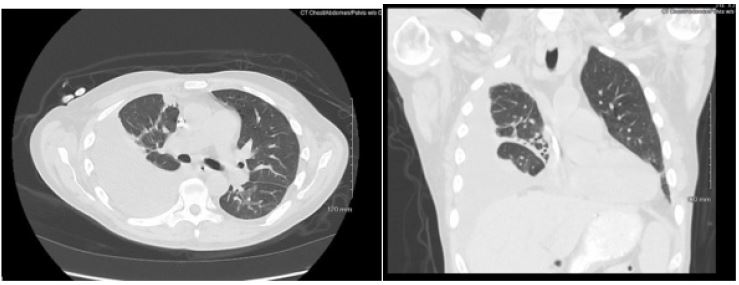

Patient presented with elevated blood pressure at 174/88. BMP was significant for Na 133, K 4.6, BUN 29, Cr 5.3. CMP is significant for Albumin 2.5. CBC was significant for Hb 8.7, Hct 25.0. D-dimer was found elevated at 4,670. PT and INR were normal. ABG significant for pH 7.52, pCO2 31.4, HCO3 25.3. A chest x-ray on admission demonstrated a large right-sided pleural effusion, contributing to significant compressive atelectasis of the right lung and leftward deviation of the mediastinal structures. Thoracentesis was performed, which demonstrated blood- tinged serosanguinous fluid. Transthoracic echocardiogram demonstrated EF 60-65%, LV diastolic dysfunction, with trace mitral and tricuspid regurgitation, and was negative for pericardial effusion. CT Chest demonstrated a large volume right-sided pleural effusion without pneumothorax, with extensive progressive atelectasis throughout the right lung. There was also a trace left-sided pleural effusion and pleural thickening with round atelectasis in the posterior left lower lobe, as well as minimal interstitial edema in the left lung. A chest tube was placed with consistent drainage throughout admission. Repeat chest x-rays continued to demonstrate pleural effusion. Thoracotomy, decortication, and pleurodesis were performed with Video-Assisted Thoracoscopic Surgery (VATS), with significant improvement of symptoms. The pleural fluid biopsy was negative for malignancy and revealed fibrocollagenous tissue with chronic inflammation and a few reactive epithelial cells. Thorough review of the patient’s medication list led to suspicion that the patient’s 50 mg Hydralazine three times a day may be the offending agent. Anti-histone antibody titers were found to be elevated at 3.7. Free Kappa and Lambda light chains were elevated. Antinuclear Antibody (ANA) titers were found to be negative. Hydralazine was discontinued, and after chest tube removal and improved chest x-ray, the patient was discharged home. It was recommended that the patient follow up with their primary care provider and rheumatologist.

Figure 1: Chest radiographs demonstrating large right sided pleural effusion, and small left lower pleural effusion.